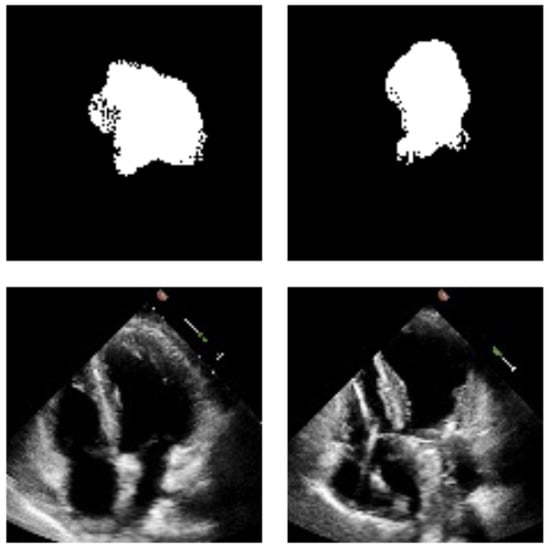

4.2. Qualitative Analysis

3.5.1. Visual Inspection of Segmentation Results